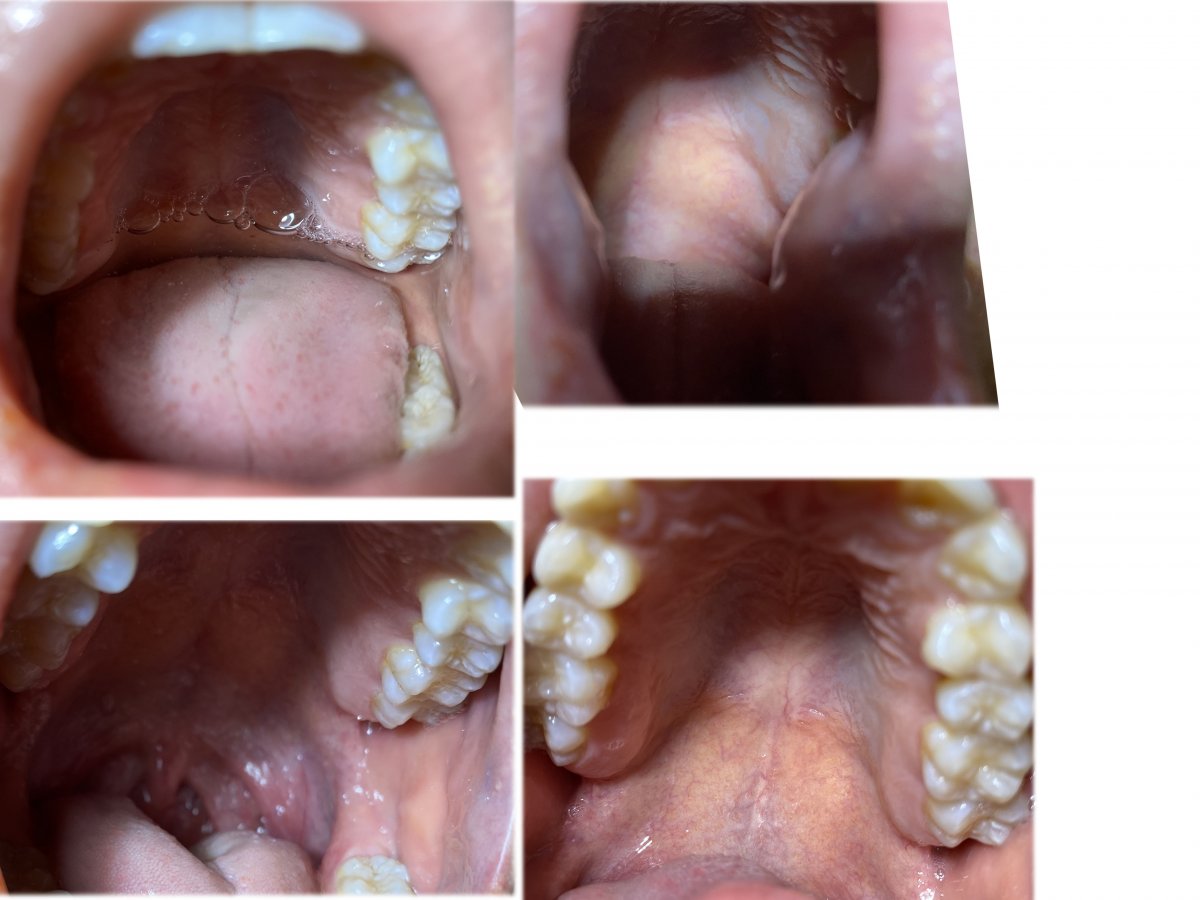

The starting point of this project is me going to see the dentist. I found out the mouth could be a interesting idea to research as a shared space. Here's some visual primary research.

My mouth scanning

kept receipts of seeing the dentist